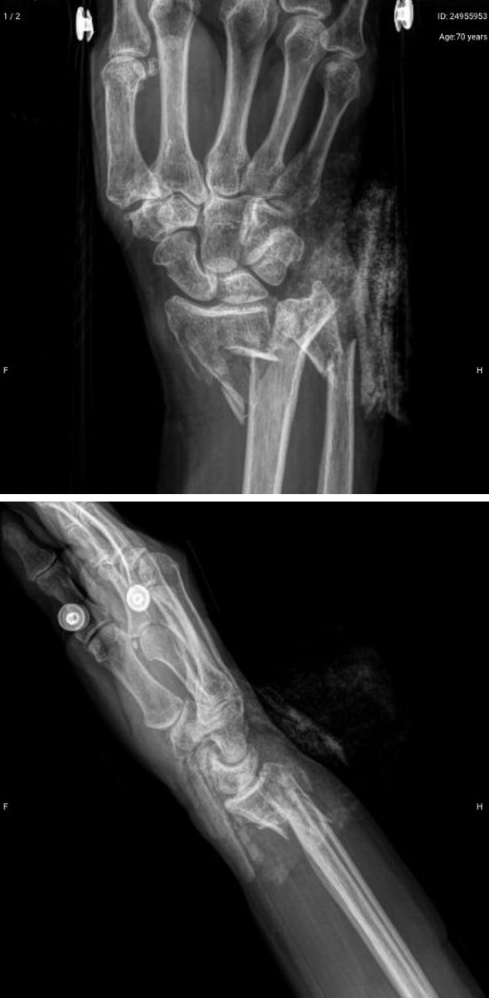

Después